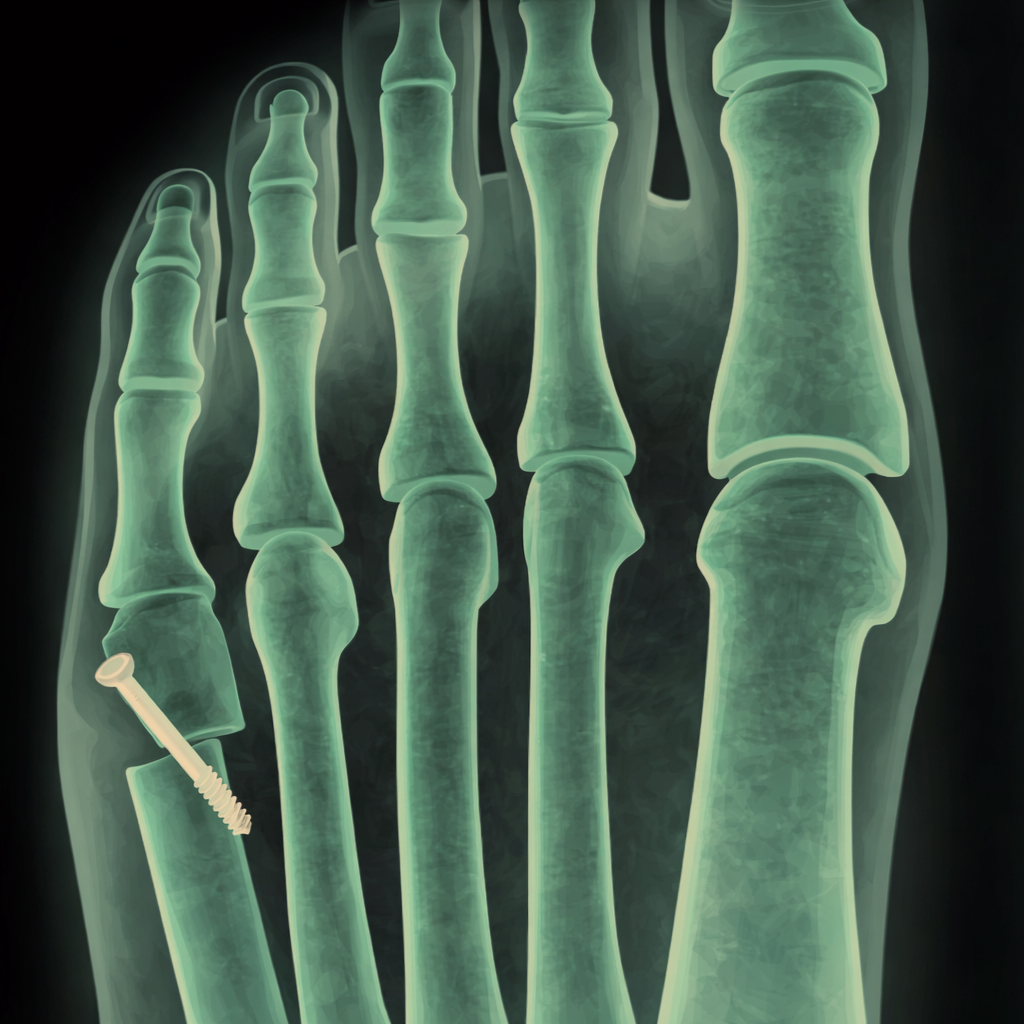

Bunion Correction and Forefoot Procedures Bunion Correction Bunion Correction 1st MTP joint decompression osteotomy 1st MTP joint decompression osteotomy Cheilectomy Cheilectomy Plantar Plate Repair Plantar Plate Repair 5th Metatarsal Osteotomy (Bunionette Correction) 5th Metatarsal Osteotomy (Bunionette Correction) Metatarsal Osteotomy Metatarsal Osteotomy Hammertoe Correction Hammertoe Correction Sesamoidectomy Sesamoidectomy